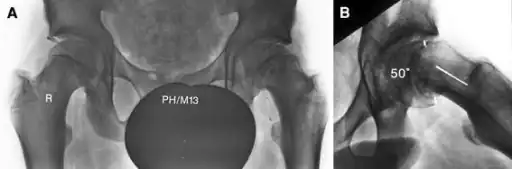

The diagnosis requires x-rays of the pelvis, with anteriorposterior (AP) and frog-leg lateral views.[12] The appearance of the head of the femur in relation to the shaft likens that of a "melting ice cream cone", visible with Klein's line. The severity of the disease can be measured using the Southwick angle.

Slipped capital femoral epiphysis before surgery

Xray showing SCFE